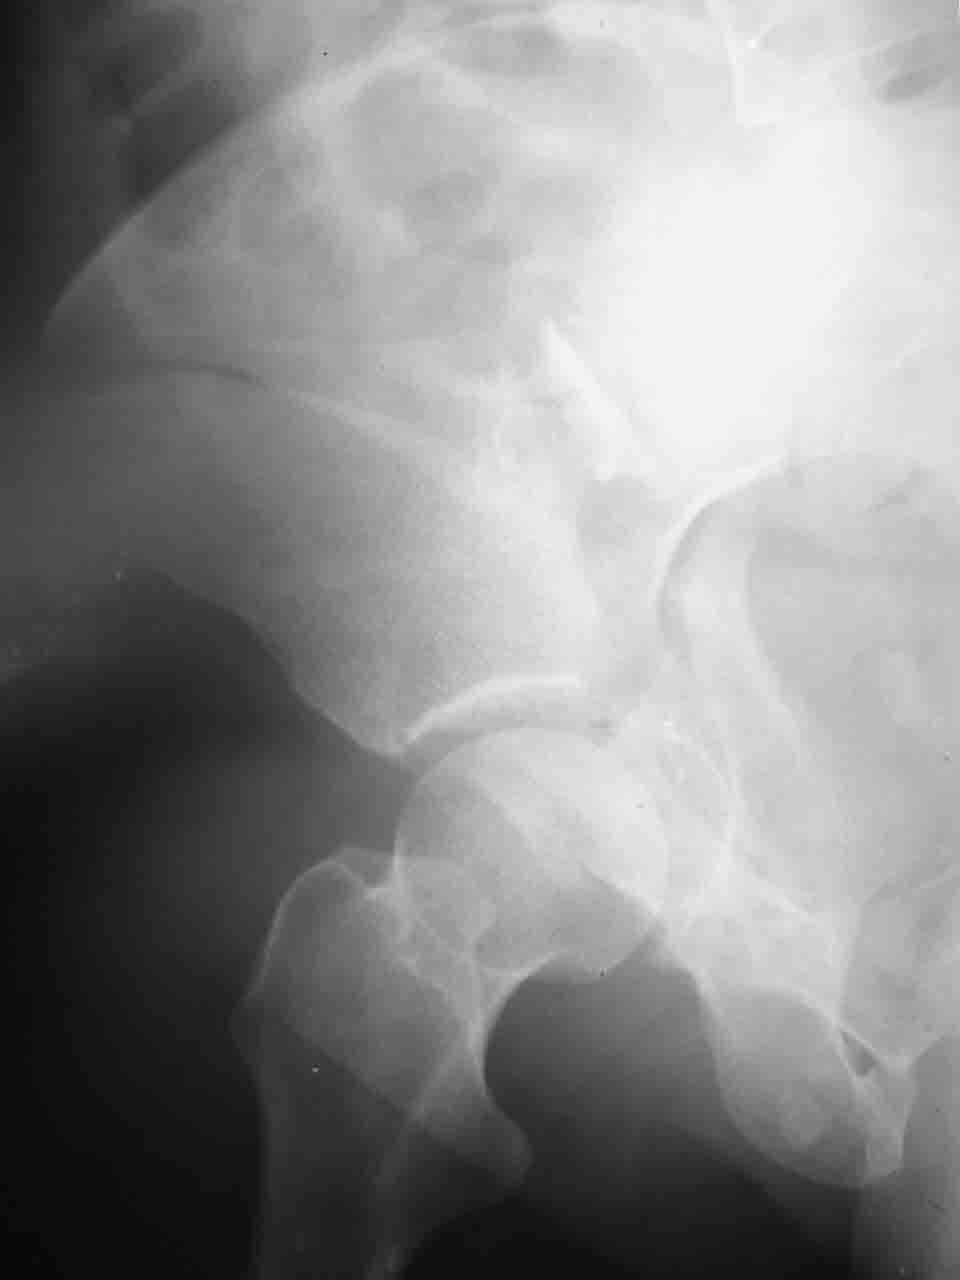

Уважаемые коллеги,43 летний мужчина, попав в автоаварию 13.10.2004, получил оскольчатый перелом обеих колонн левой вертлужной впадины.

На рентгенограммах - высокий двухколонный перелом вертлужной впадины с нарушением конгруэнтности, имеется обратная клиновидность суставной щели.

Причиной обращения к сообществу были возникшие непосредственно после операции сомнения и разочарования полученным качеством репозиции: а надо ли было трогать перелом вообще, репозиция передней колонны технически была очень сложна для меня, хотя реконструкции была в той же последовательности, что Д-р А.В.Рунков рекомендовал, в какой-то момент безуспешных манипуляций стал думать о *вторичной конгруэнтности*, которую не так давно обсуждали на

Логика подсказывает, что все-таки лучше иметь анатомически полноценную впадину, хотя ранее упоминалось состояние вторичной конгруэнтности и одно наблюдение у меня есть, когда у больного с полностью нарушенной анатомией впадины и подвывихом головки бедра кзади и кверху боли отсутствовали при относительно достаточном для стиля жизни больного объёме движений. Но это только одно наблюдение и кроме перелома впадины у этогобольного была и тяжелая ЧМТ в анамнезе. Основываясь на формулировке структуры ацетабулюм Э. Летурнеля - как перевернутой буквы Y, впадина для полноценной функции сустава должна иметь сферичность, соответствующую размеру головки бедра и если один из компонентов в дефиците, то функциональные последствия рано или поздно проявятся.